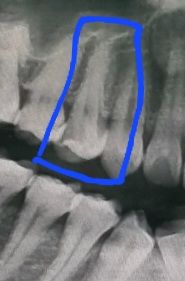

이쪽치아를 신경치료중인데 지금 1차치료후 2차치료를 받으러가는데 신경치료끝나고 바로 사랑니 발치해도 되는지 궁금해서 여쭤봅니다.

상관 없습니다. 현재 부위와 사랑니는 직접적으로 맞닿아 있지 않아 큰 부담이 되지 않습니다. 불편감만 크지 않다면 신경치료를 하는 도중에 사랑니를 발치하는 것은 전혀 문제가 되지 않습니다.

사랑니 발치는 아무때나 하셔도 크게 문제가 되진 않을것같습니다. 신경치료 마무리 하고 나서 하셔도 되고 그전에 하셔도 상관없습니다.

사랑니가 신경치료하는 치아와 같은 우측 방향이라면 발치를 해도 괜찮지만 좌측이라면 식사문제로 어려울수 있습니다.